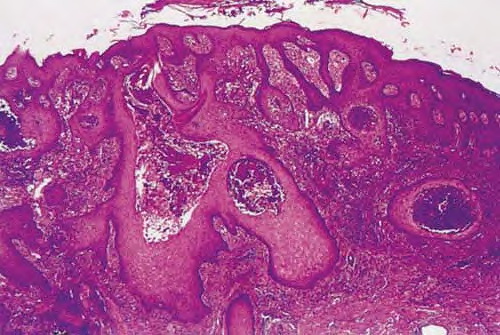

Poroma=شزن=تورم بسبب إفراز غدي POROMA The term poroma refers to a group of rare cutaneous appendage tumors composed of cells (cuticular and poroid cells) similar to those of the acrosyringium. Poromas are traditionally subcategorized histopathologically based on their location in relation to the epidermis into three main variants; namely, hidroacanthoma simplex, eccrine poroma, and […]